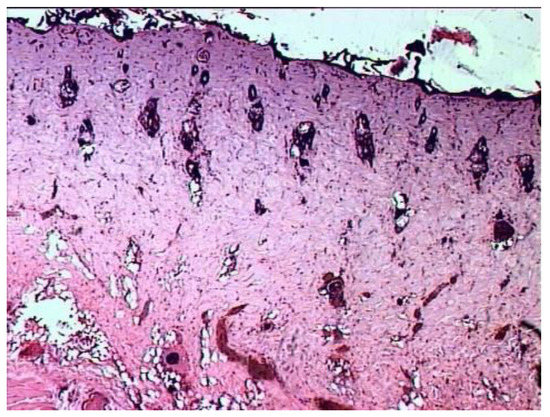

According to the results of histological examination, it was found that the first day after the injury, the histological picture in the edges of wounds in animals of all three groups had no differences (Figure 1). In all preparations, there is a lesion of the epidermis (necrosis and necrobiosis), dermis (papillary and mesh layers), manifested by the loss of the usual fibrous structure of the connective tissue of the dermis and transformation collagen fibers into a solid homogeneous mass, as well as edema and hemorrhages in loose connective tissue and adipose tissue located above the layer of the skin’s own muscle.

The blood vessels passing through here are often also necrotic, containing red blood clots. The muscle fibers of the skin’s own muscles are in a state of dystrophy: swollen, often vacuolated. There are no cores in individual fibers. In the loose connective tissue located under the muscle layer, there is fullness, puffiness, as well as an increased number of cells, among which leukocytes and macrophages predominate.

Figure 1. Histological picture of the wound on the first day after the burn (typical picture for rats of all groups). Deep burn with necrosis of the epidermis, papillary and mesh layers of the dermis, as well as necrobiosis of the muscle fibers of the skin’s own muscle. Stained with hematoxylin and eosin. magn. ×50.